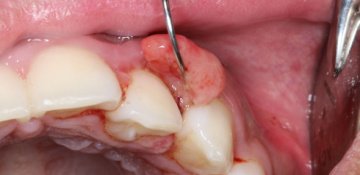

• Wisdom Tooth Extraction: This common procedure involves removing the third molars (wisdom teeth) which can cause pain, overcrowding, or infection if they don't erupt properly.